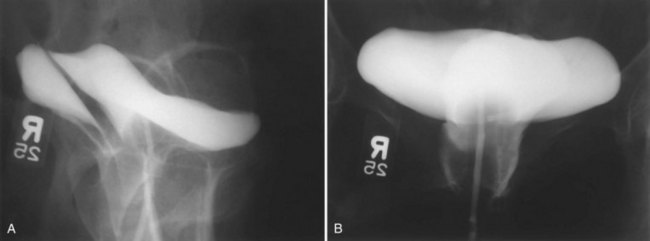

There are multiple variations to transvaginal fistula repair, including those originally described by Latzko in 1914. The Latzko high-partial colpocleisis is a very popular approach among some reconstructive surgeons, with reported success rates in excess of 90% (Kaser, 1977; Tancer, 1980). This approach may not be as successful as the vaginal flap technique for large obstetric fistulae (Elkins et al, 1988). In this procedure, the fistula tract is isolated, and the tissue surrounding the VVF tract is denuded of vaginal “epithelium” circumferentially for a distance of 1 to 2 cm. Care is taken to avoid deeply “denuding” the vaginal tissues to avoid entry into the bladder or perivesical fascia. The denuded areas are then reapproximated over the fistula tract with a series of interrupted absorbable sutures. Sutures are not placed into the bladder wall or vesical mucosa. The edges of the vaginal wall are then reapproximated as a second layer, creating a partial colpocleisis in some patients. Advantages of the Latzko procedure include minimal blood loss, no need for ureteral reimplantation (even for a fistula adjacent to the ureter, because sutures are not placed through the bladder), and a short convalescence. Potential disadvantages include the possibility for vaginal shortening (Enzelsberger and Gitsch, 1991), as well as the creation of directly overlapping suture lines.